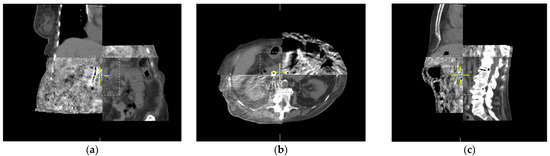

An extension of CT technology for cone-beam CT (CBCT), developed by David Jaffray [29,30], was utilized on the treatment machine by taking advantage of onboard imagers that provided pre-treatment CT-like images to match the planned treatment volume by image fusion, as shown in Figure 1. This provided the initial impetus for IGRT.

Figure 1.

Registration of cone beam CT obtained in treatment position on treatment machine to planning CT scan for abdominal RT in three dimensions: (a) coronal, (b) axial, and (c) sagittal slices each illustrate the registration between the CT scans used on the treatment machine to ensure alignment.